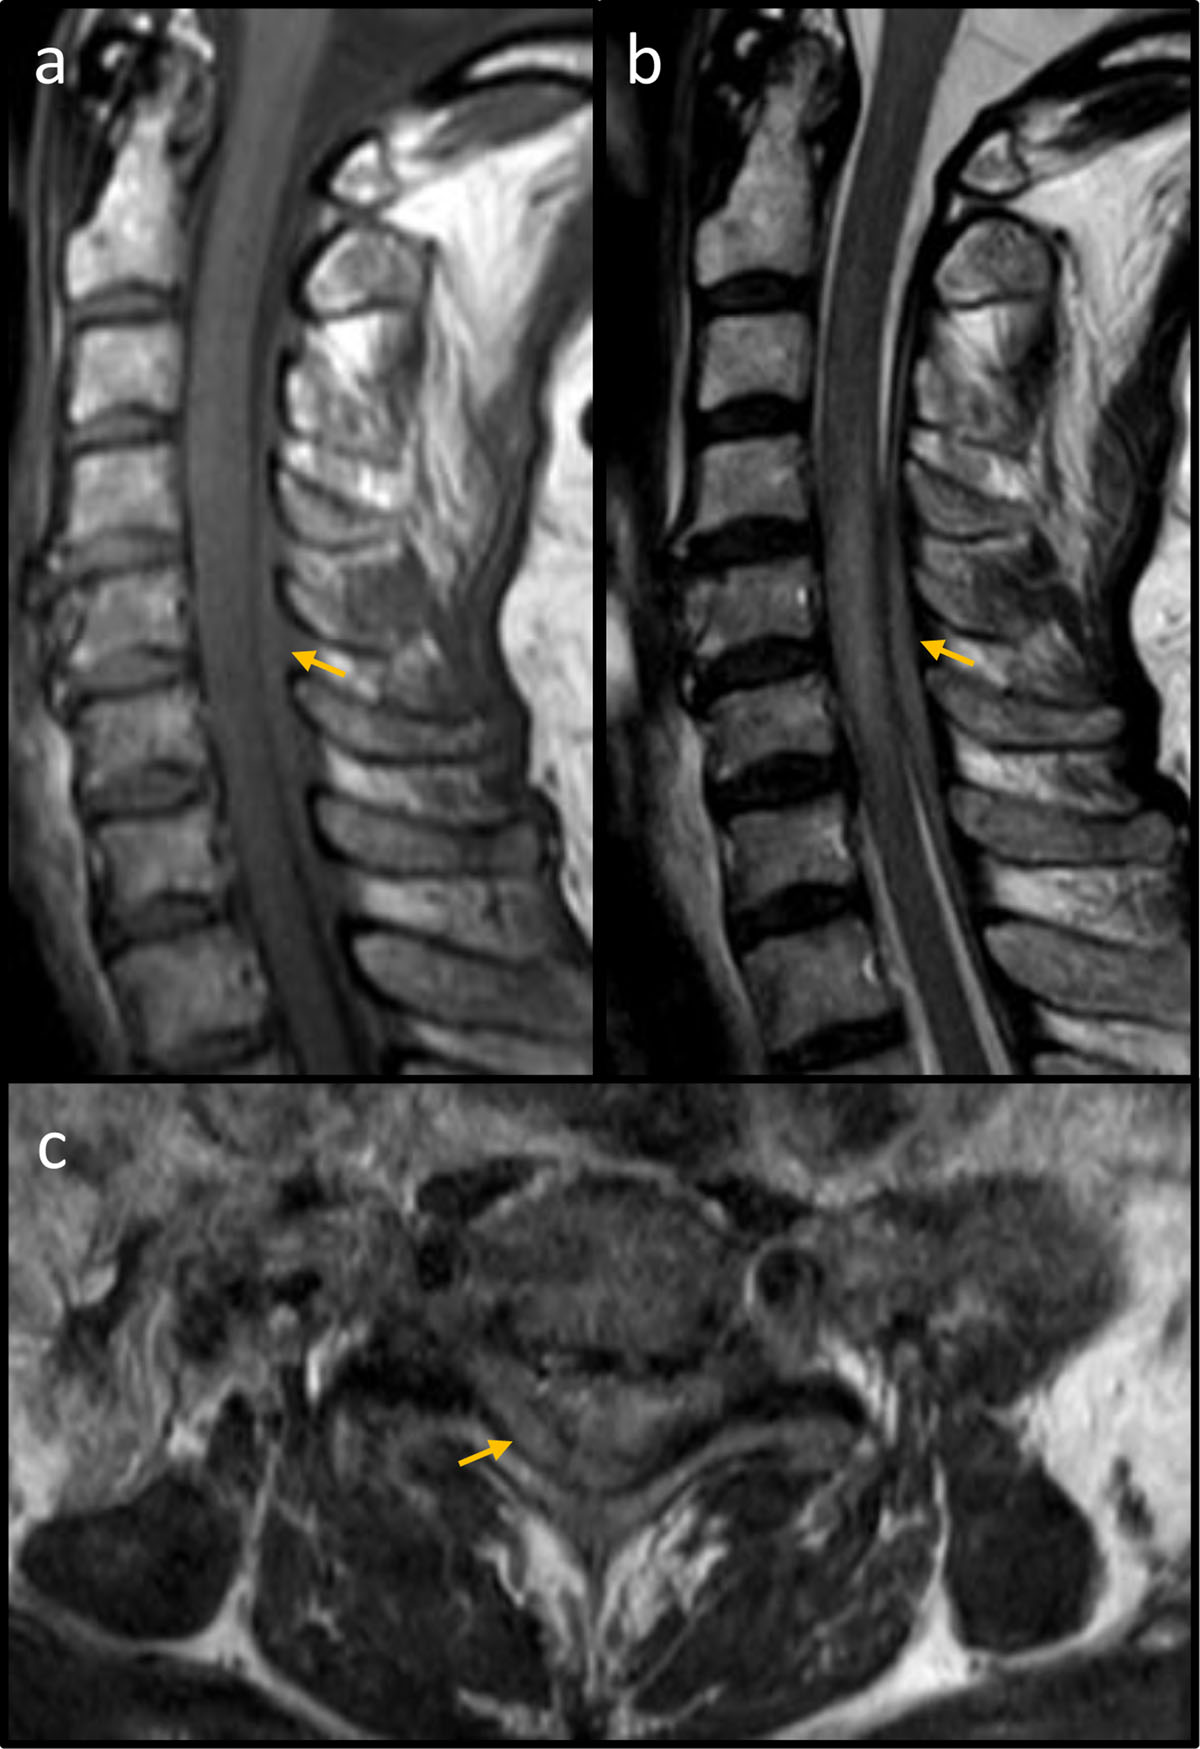

Figure 1

MRI of the cervical spine. (a) Sagittal T1 spin echo demonstrating an iso-intense space-occupying lesion (yellow arrow) restricted to the posterior epidural space. (b) Sagittal T2 spin echo showing a slightly hyper-intense mass (yellow arrow) in the posterior epidural space with corresponding myelopathy. (c) Axial T2 spin echo at vertebral level C6 showing a predominantly right-sided mass in the posterior epidural space (yellow arrow).